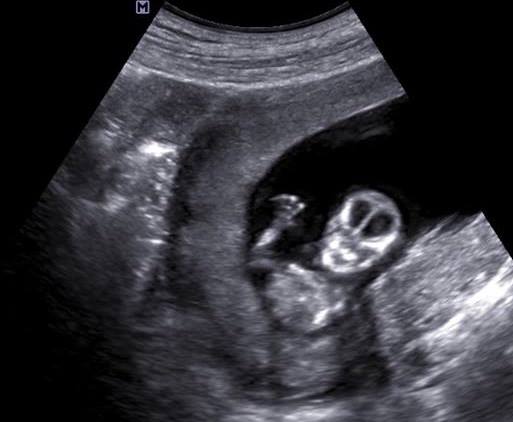

@nelka33 no u nas to bolo zabavne, lebo rano mi to Cickova nezdvihala a tak som volala sestricke co je na recepcii...a sme sa dohodli, ze do pol 9 pridem...potom ked som tam prisla, tak vsetci vysmiati, ze ci to myslim vazne, ze dnes na Valentina dojdem pozitivna ;)...tak mi vzali krv a isla som na sono, lekar ma ubezpecil, ze to je este prilis skoro a nic tam nemusi byt vidno...ale potom ked dal lupu, tak sme videli malu 2mm bodku....tak som odtial odchadzala s dobrou naladou a potom o pol 3 mi volali, ze mi gratuluju, ze vysledky krvi su pozitivne...teraz v piatok mam opat kontrolu, tak som zvedava ;)

@aysuna ahojte takze na ultrazvuku nic nebolo vidiet a krv mi vysla pozitivne ale hodnota HCG je dost niska iba 50 takze mi nic nevedeli povedat a otporucili mi aby som isla ku svojej Dr na buduci tyzden niekedy v utorok na kontrolne testy takze zatial je to pol na pol ..takze zasa cakat....ale pozitivne je ze som prvi krat oficialne tehu tak uvidime ako to dopadne